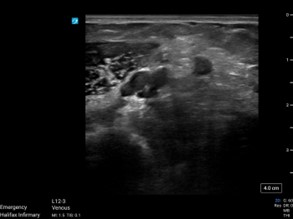

Brachial Vein(Click on images for both videos)

Brachial vein to the R also demonstrated no compressibility or flow.